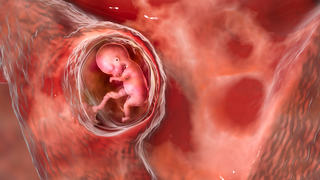

TTTS is a rare complication that happens only in identical twin pregnancies. These twins usually share one placenta but have separate amniotic sacs. These twins are called monochorionic diamniotic twins. Tiny blood vessels connect their blood supplies. If the blood supply between the twins is not shared evenly, TTTS can develop.

In this condition, one twin, called the donor, gets less blood. On the other hand, the recipient twin gets too much. In TTTS, the donor twin grows more slowly and has less amniotic fluid. The recipient twin’s heart has to work harder due to excess blood. TTTS occurs by chance and affects about 15% of identical twin pregnancies.